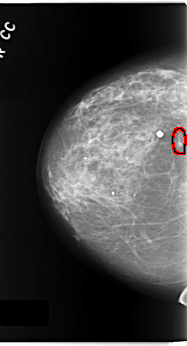

C_0171_1.LEFT_MLO

FILE: C_0171_1.LEFT_MLO.OVERLAY

TOTAL_ABNORMALITIES 1

ABNORMALITY 1

LESION_TYPE MASS SHAPE ARCHITECTURAL_DISTORTION MARGINS SPICULATED

ASSESSMENT 2

SUBTLETY 5

PATHOLOGY BENIGN

TOTAL_OUTLINES 1

BOUNDARY